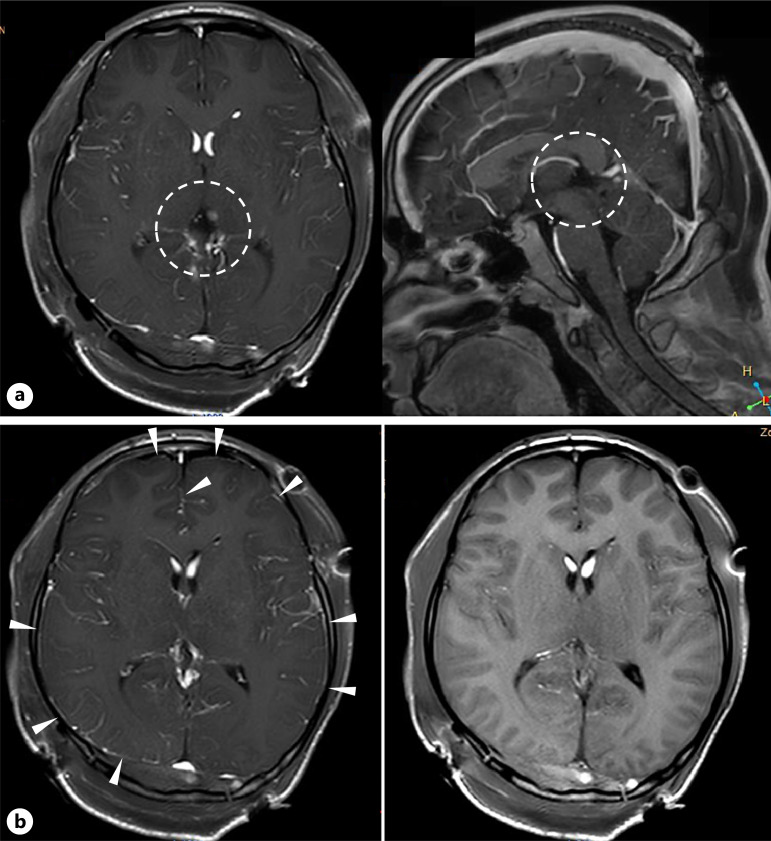

Case presentation: A 15-year-old boy presented with a 2-month history of persistent headaches. Computed tomography revealed a calcified mass lesion in the pineal region with low-density areas in the lateral ventricles. Magnetic resonance imaging (MRI) demonstrated a complex lesion in the pineal region and high T1 signal intensity bilaterally in the anterior horns of the lateral ventricles, suggestive of a ruptured teratoma. The patient underwent surgical resection. Postoperatively, he developed mild fever, severe headache, ocular pain, decreased vision, diplopia, and neck rigidity. Contrast-enhanced MRI revealed faint meningeal enhancement, consistent with aseptic meningitis. Symptoms gradually improved with steroid therapy.